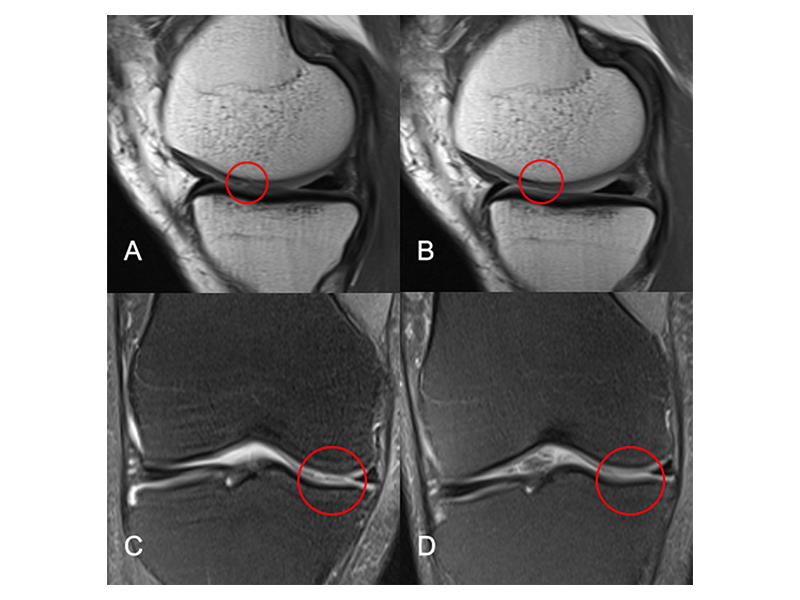

图2核磁影像评估全厚软骨缺损在治疗5年前后的变化

A、C注射SVF前的股骨内侧和胫骨冠状位和矢状位图像,圆圈显示全厚软骨缺损。B、D注射SVF 5年后的股骨内侧和胫骨冠状面和矢状面图像。圆圈区域的全厚软骨缺损消失,软骨边缘光滑[4]。